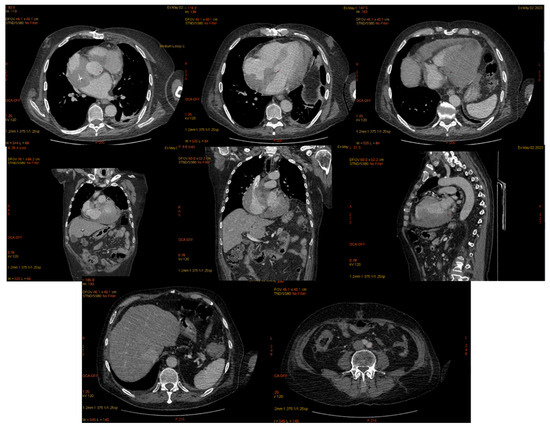

| June 2022 | first extramedullary relapse left testicular—diagnostic immunophenotyping of semen | HyperCVAD Block A radiotherapy, 24 gy/12 sessions for the scrotal sac and the lymph nodes along the left spermatic vein result: complete metabolic remission petct |

| January 2023 | second extramedullary relapse bilateral ocular left eye clinically, imaging, and biopsy demonstrated right eye demonstrated by imaging | methotrexate, asparaginase, calcium folinate radiotherapy, 30 gy/15 sessions result: imaging complete remission |

| 2 May 2023 | third emr: cardiac and colonic mass (+cns?) | nelarabine+cyclophosphamide+ etoposide |